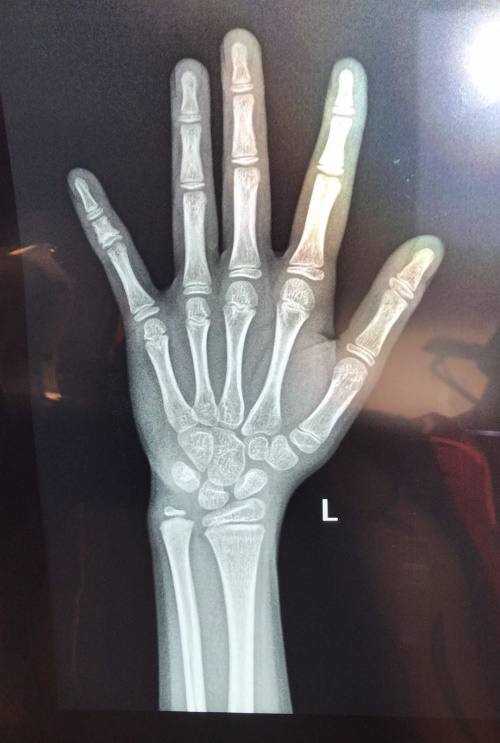

这不是惊悚片,是朋友家10岁女儿的手指骨龄X光片。之所有朋友要带女儿查骨龄,是因为她发现女儿有提前发育的特征,检查结果显示骨龄超半年。你知道吗?除了孩子提早发育时,当孩子比同龄孩子矮很多时,也是需要测骨龄的!

骨龄是骨骼年龄的简称,通常要拍摄人左手手腕部的X光片,医生通过X光片观察左手掌指骨、腕骨及桡尺骨下端的骨化中心的发育程度,来确定骨龄。据北京儿研所的医生表示,骨龄一般只针对小学阶段的孩子。